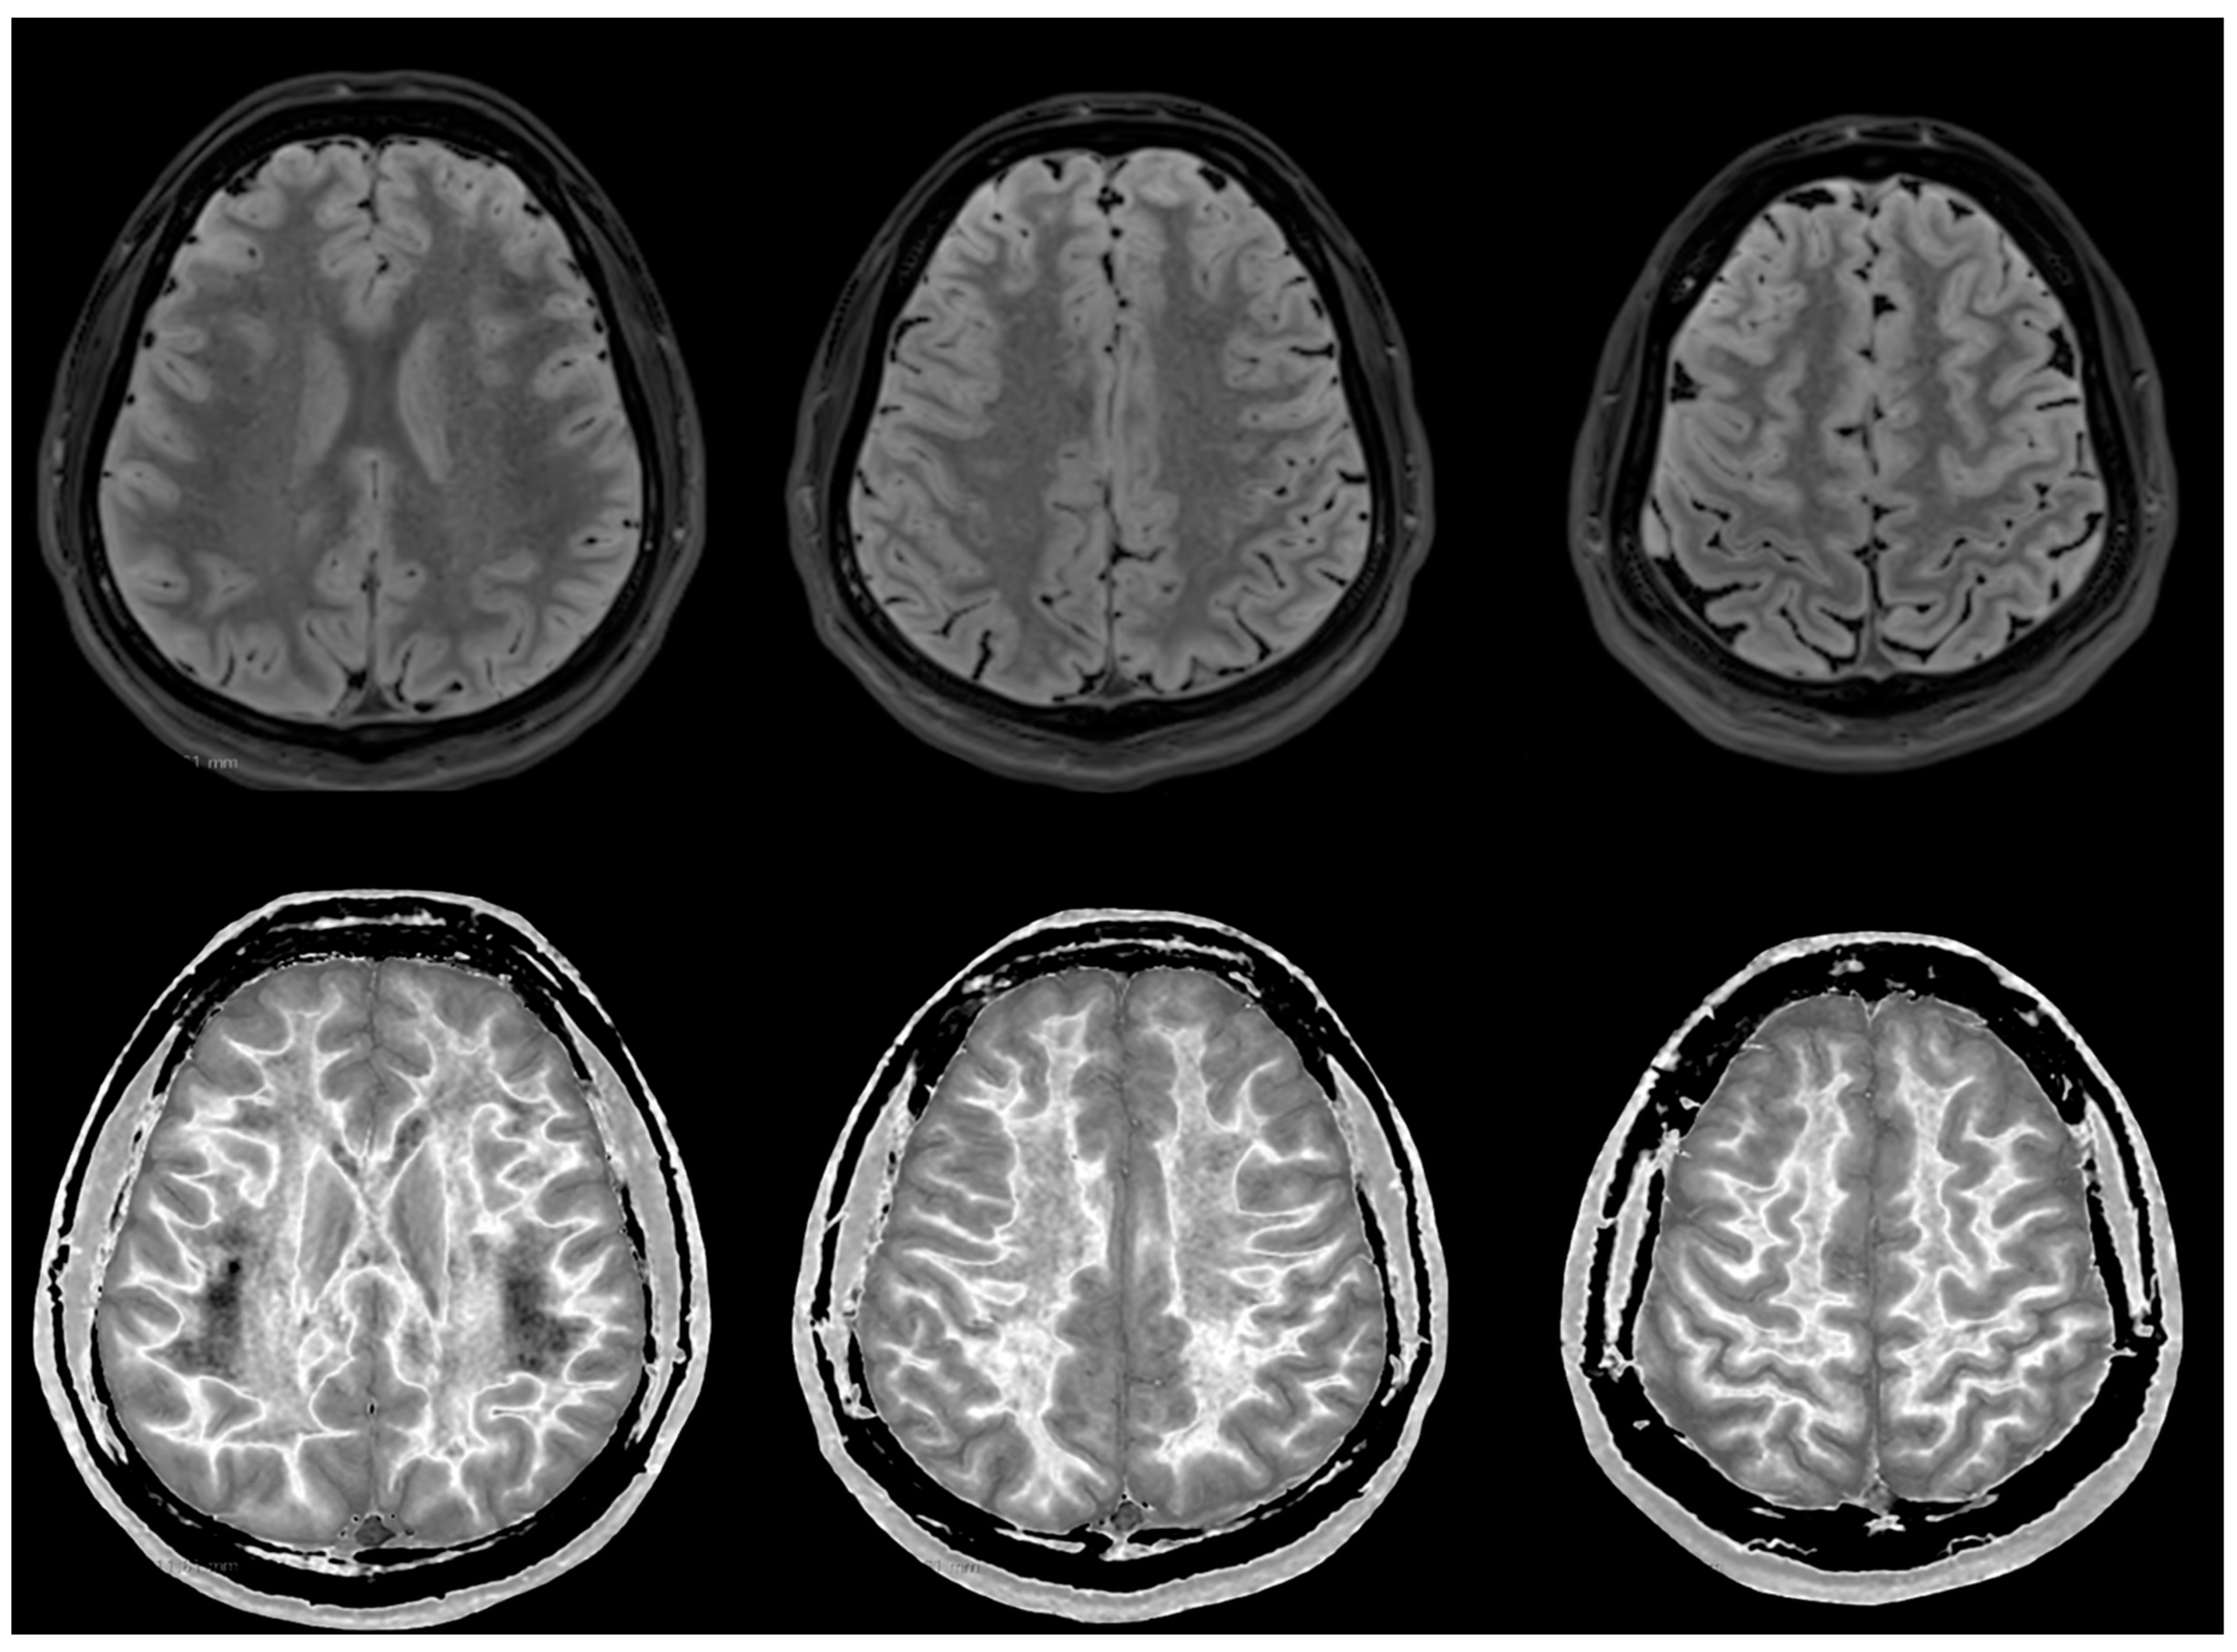

Figure 6 and Figure 7 show T2-FLAIR images (upper rows) with positionally matched dSIR images (lower rows). No abnormalities are seen in the white matter on the T2-FLAIR images, but very extensive high signal abnormalities are seen in the white matter of the corresponding dSIR images. There is relative sparing of the anterior central corpus callosum and, to a lesser extent, the posterior central corpus callosum. There is also some sparing of the peripheral white matter in the cerebral hemispheres.

Overall, the MRI findings in Case 2 are very similar to those in Case 1, as shown in Figure 4 and Figure 5. They have been described as a whiteout sign. This often involves 80% or more of the white matter in the cerebral and cerebellar hemispheres having an abnormal high signal appearance.

Figure 7. Case 2 was examined two years after his asphyxial episode. Comparison of positionally matched T2-FLAIR images (upper row) and narrow mD dSIR images (lower row). No abnormality is seen on the T2-FLAIR images, but there are extensive areas of high signals in the central white matter of the brain (lower row). Only some of the peripheral white matter on the lower images appears darker and looks more normal on the dSIR images.